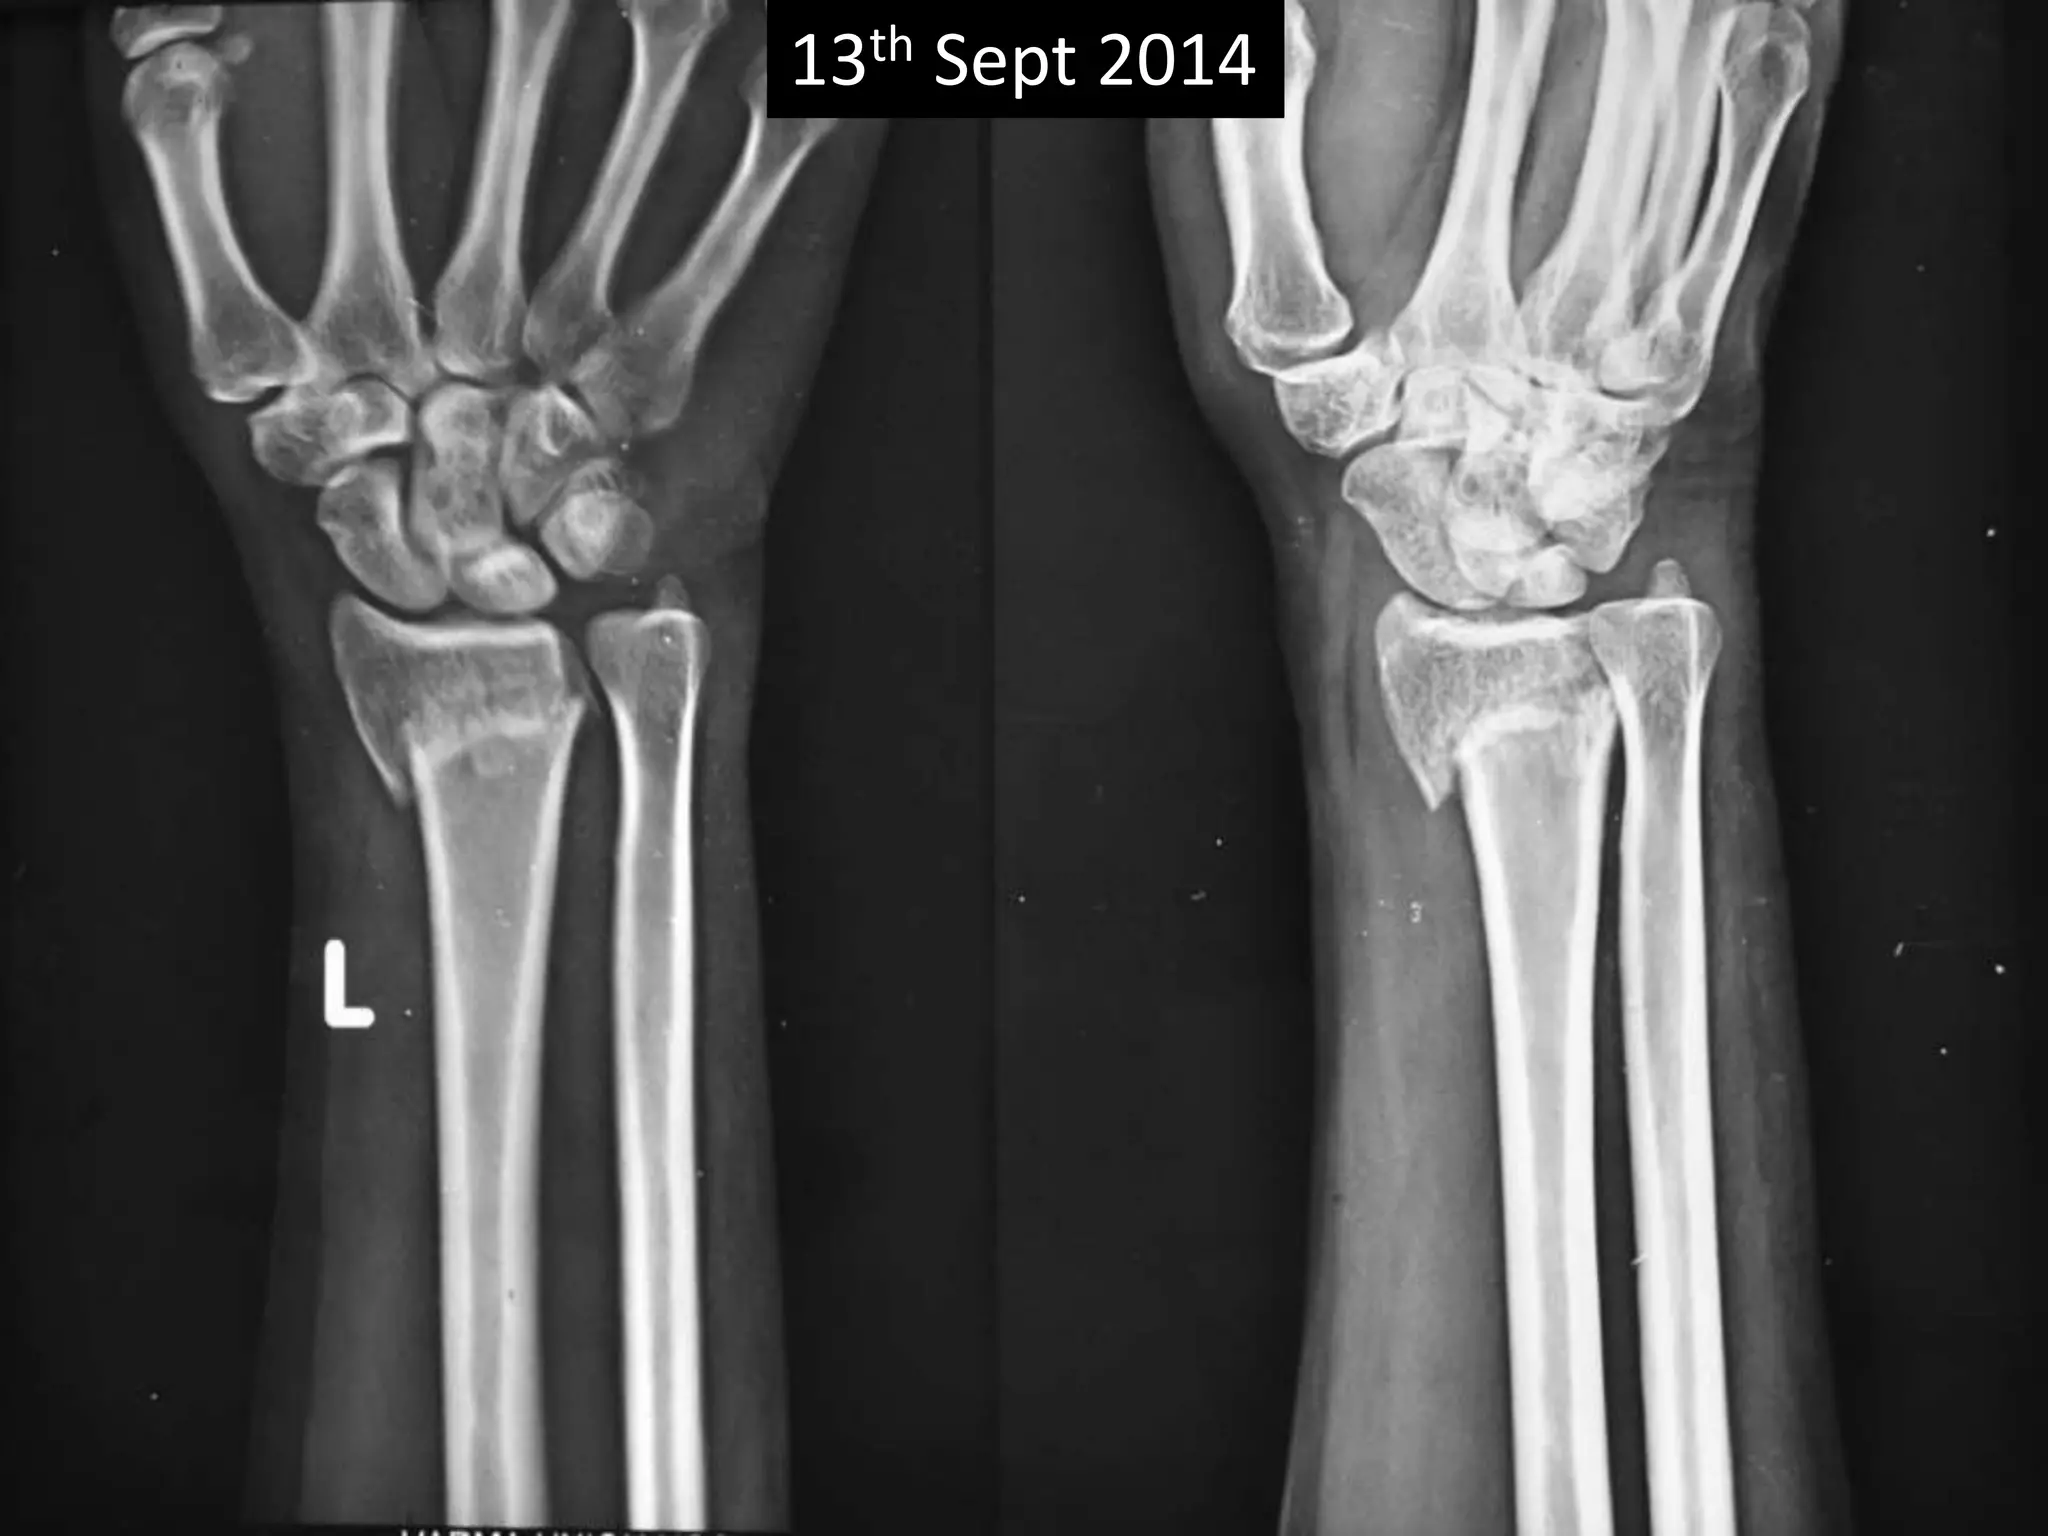

Case three

• 40 years old Female,

• Sustained fracture lower end radius on 13th Sept

2014.

• Received no treatment.

• No co-morbidity.

• Chief complaint was deformity of wrist.

• X-rays on 11th Nov 2014 showing delayed union

• Clinically no disability.

• Patient refused corrective surgery.

13th Sept 2014

Case three •40 years old Female, • Sustained fracture lower end radius on 13th Sept 2014. • Received no treatment. • No co-morbidity. • Chief complaint was deformity of wrist. • X-rays on 11th Nov 2014 showing delayed union • Clinically no disability. • Patient refused corrective surgery.